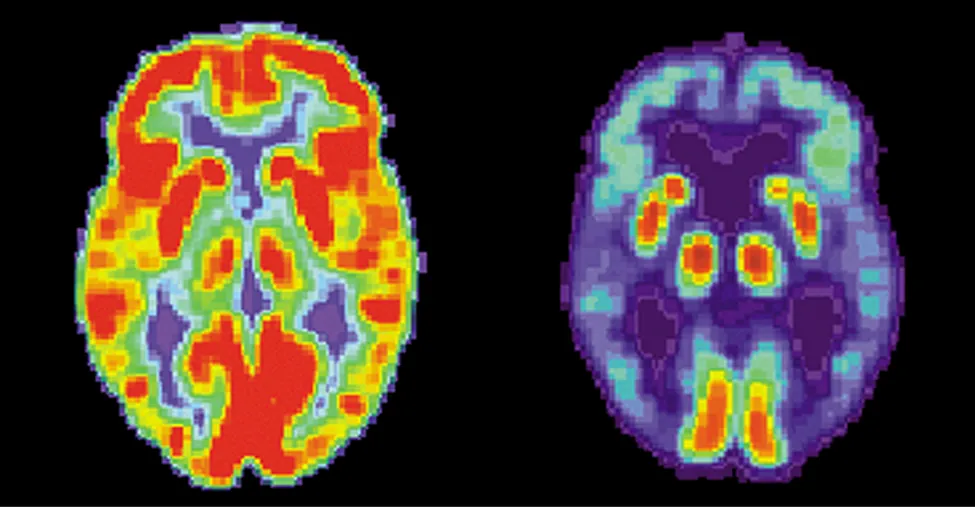

Se muestran la imagen de dos cerebros. El de la izquierda tiene muchas zonas rojas y naranjas y algunas azules. El de la derecha es mayormente azul con áreas muy pequeñas en rojo y amarillo.

Figura 10.27 Estas imágenes cerebrales se producen utilizando un radiofármaco. Los colores indican la actividad metabólica o bioquímica relativa (el rojo indica alta actividad y el azul, baja). La figura de la izquierda muestra un cerebro normal y la figura de la derecha muestra el de una persona diagnosticada con la enfermedad de Alzheimer. La imagen del cerebro normal indica una actividad metabólica mucho mayor (una mayor fracción de áreas rojas y naranjas) (crédito: modificación de obras de los Institutos Nacionales de Salud (National Institutes of Health)).